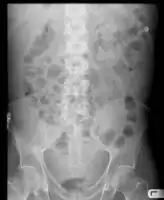

Diagnostic methodPhysical exam, ultrasound, CT scan[3]

In the developed world, the most common cause is liver cirrhosis.[4] Other causes include cancer, heart failure, tuberculosis, pancreatitis, and blockage of the hepatic vein.[4] In cirrhosis, the underlying mechanism involves high blood pressure in the portal system and dysfunction of blood vessels.[4] Diagnosis is typically based on an examination together with ultrasound or a CT scan.[3] Testing the fluid can help in determining the underlying cause.[3]

Diagnosis

Routine complete blood count (CBC), basic metabolic profile, liver enzymes, and coagulation should be performed. Most experts recommend a diagnostic paracentesis be performed if the ascites is new or if the person with ascites is being admitted to the hospital. The fluid is then reviewed for its gross appearance, protein level, albumin, and cell counts (red and white). Additional tests will be performed if indicated such as microbiological culture, Gram stain and cytopathology.[6]

Ultrasound investigation is often performed prior to attempts to remove fluid from the abdomen. This may reveal the size and shape of the abdominal organs, and Doppler studies may show the direction of flow in the portal vein, as well as detecting Budd-Chiari syndrome (thrombosis of the hepatic vein) and portal vein thrombosis. Additionally, the sonographer can make an estimation of the amount of ascitic fluid, and difficult-to-drain ascites may be drained under ultrasound guidance. An abdominal CT scan is a more accurate alternate to reveal abdominal organ structure and morphology.